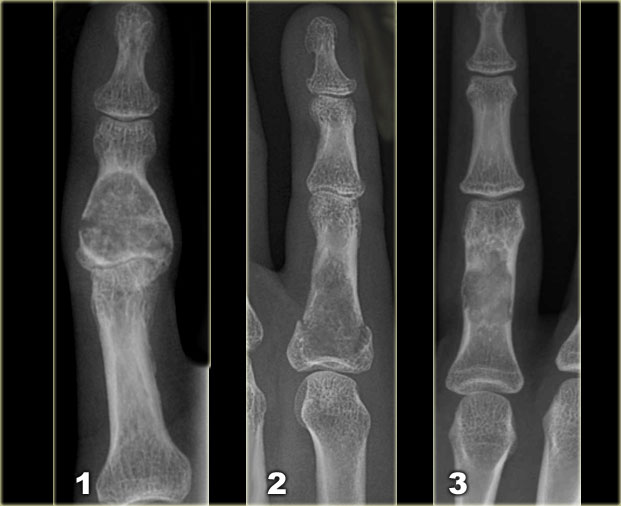

Left:

Well-defined lytic lesion with sclerotic margin and some expansion. There are fine calcifications.

This patient presented with a fracture, which is a common first presentation of an enchondroma.

Middle:

Well-defined lytic lesion without a sclerotic border also with a fracture.

Right:

Lesion with irregular cortical bone destruction. Low-grade chondrosarcoma has to be included in the differential diagnosis, but is uncommon at this specific location.